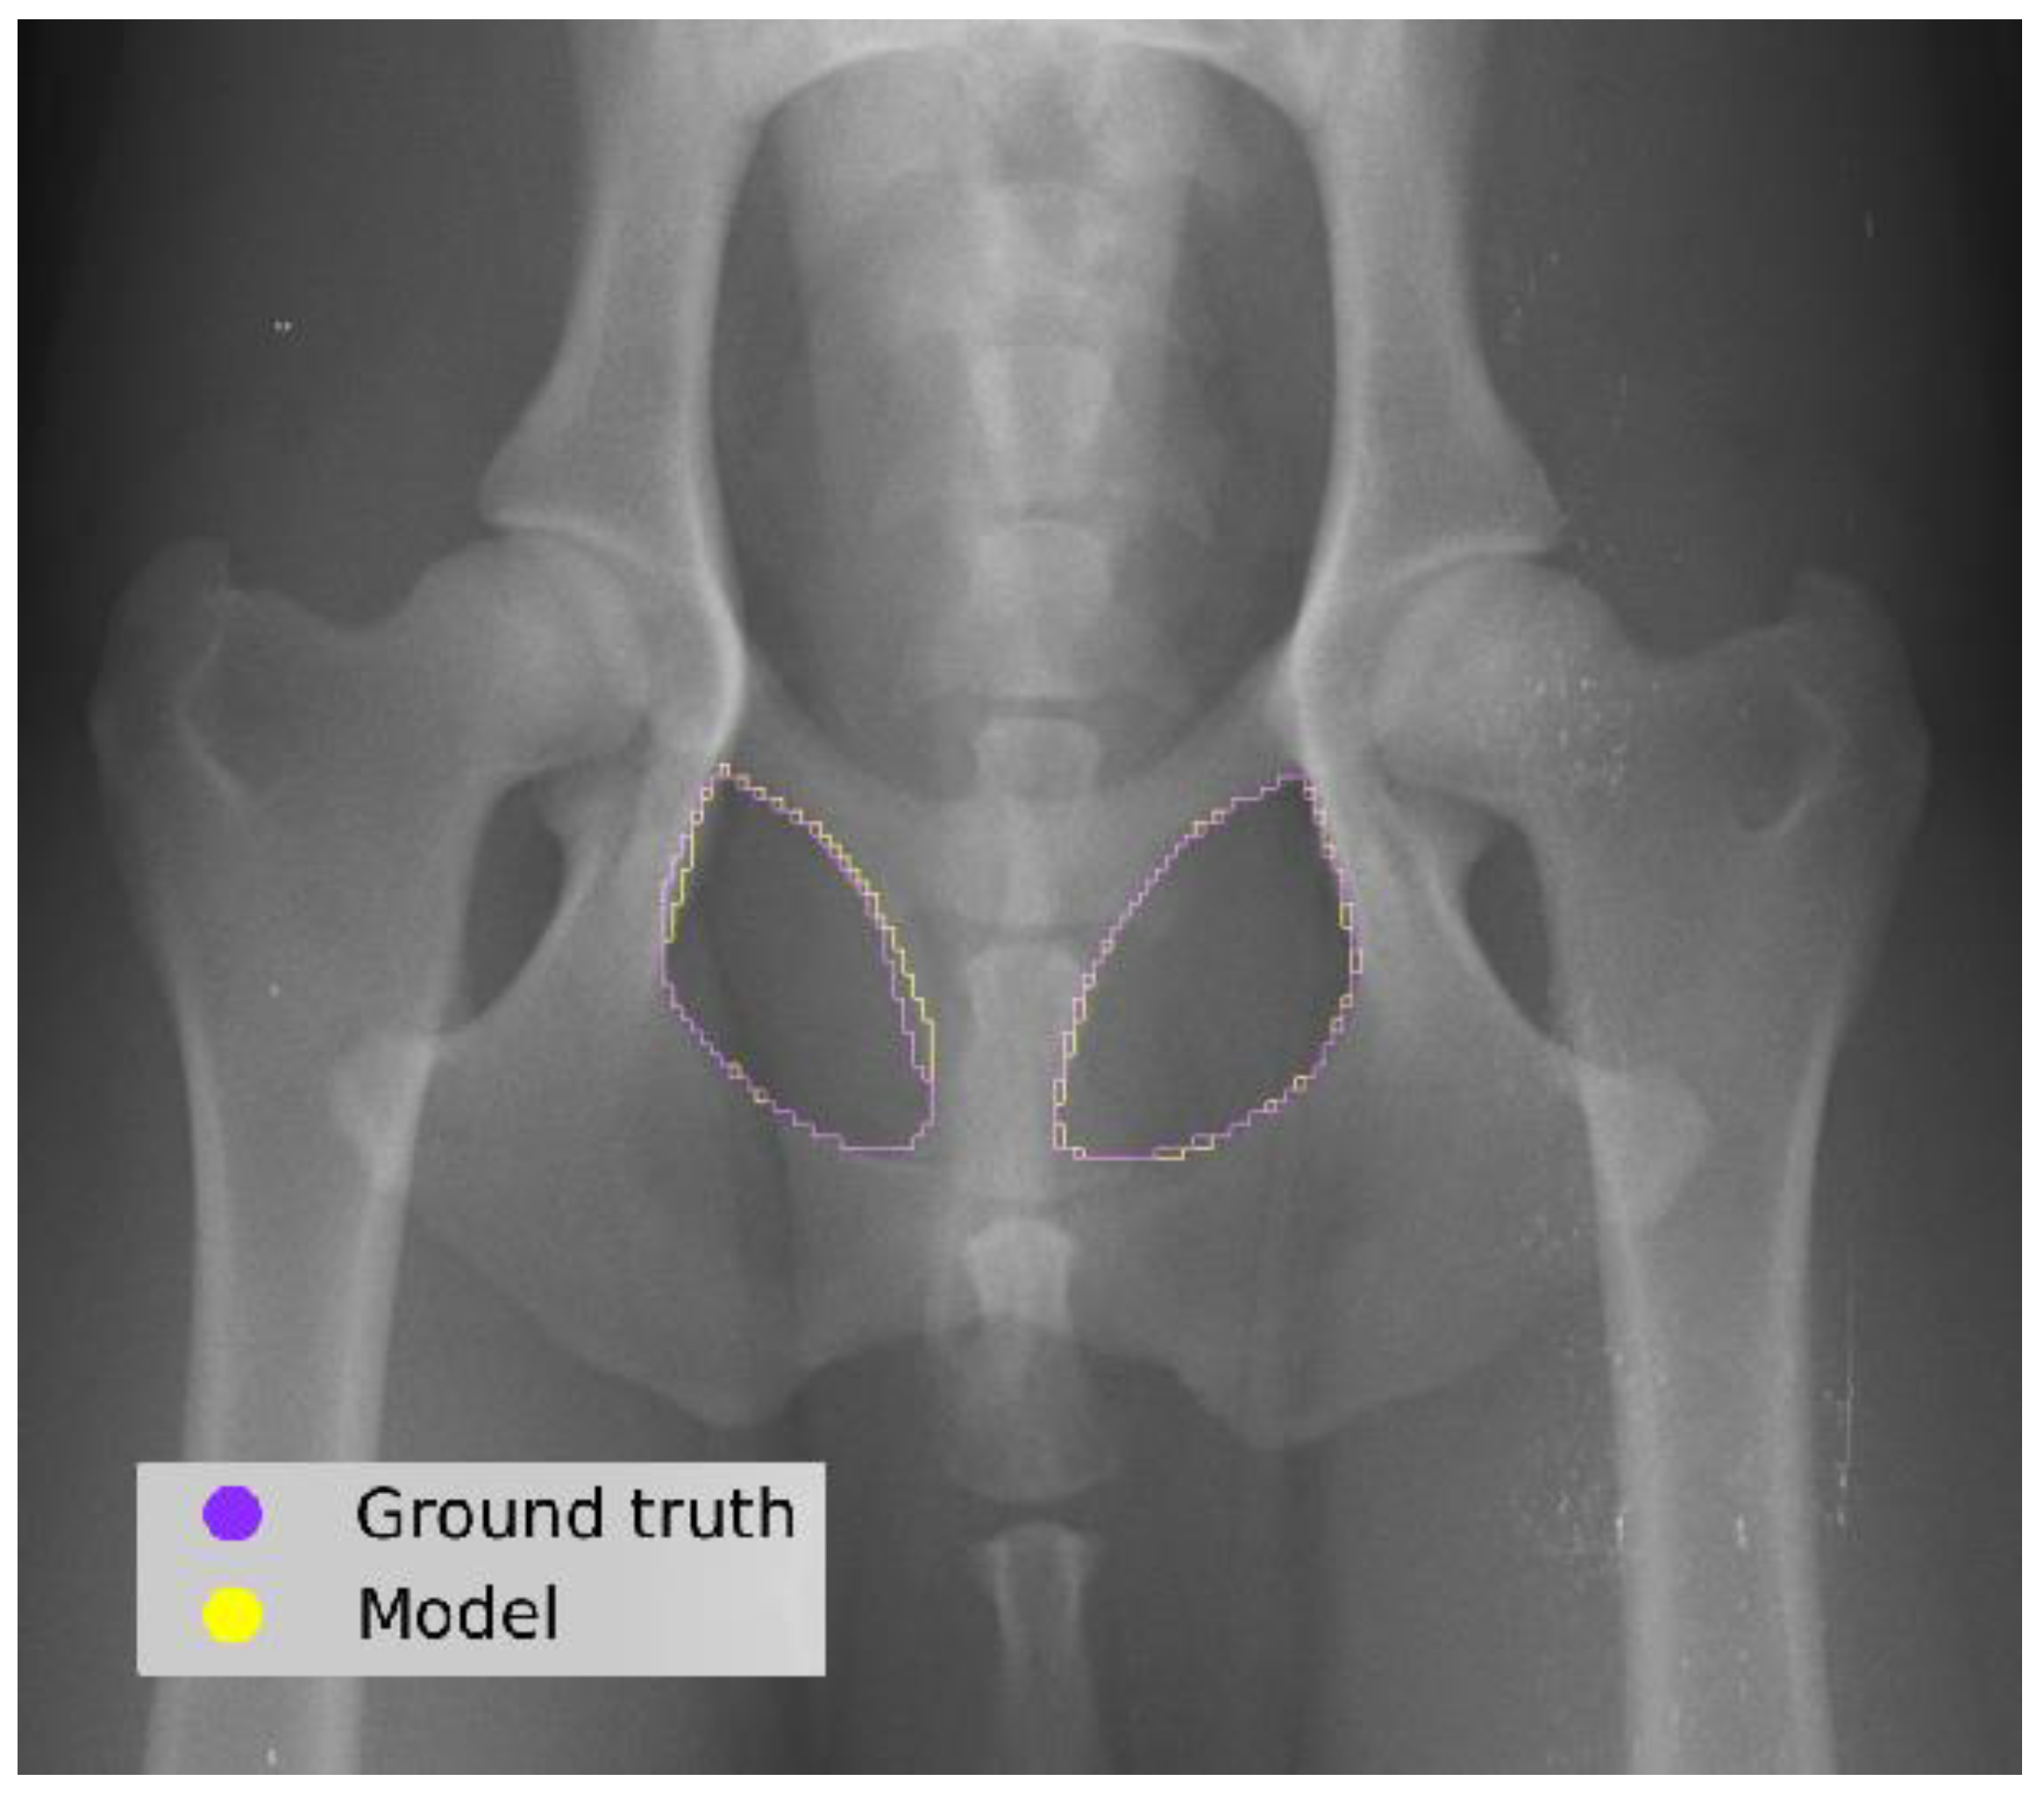

The model segmentation performance achieved a DS of 0.96 and an IOU score of 0.93 (Figure 4).

Figure 4. Comparison between the ground truth (examiner) and the predictions made by the model in a test image.